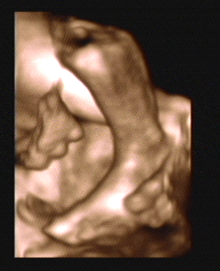

3D/4D SONOGRAPHY 18-24 WEEKS

- Normal Sonography is 2 dimensional. In 3 dimensional Sonography the information is obtained simultaneously in 3 planes (X, Y & Z).

- Highly sophisticated software reconstructs this information into a distinct 3D image.

- From a continuous 3D acquisition you get a live action view. It is known as 4D where 4th dimension is time.